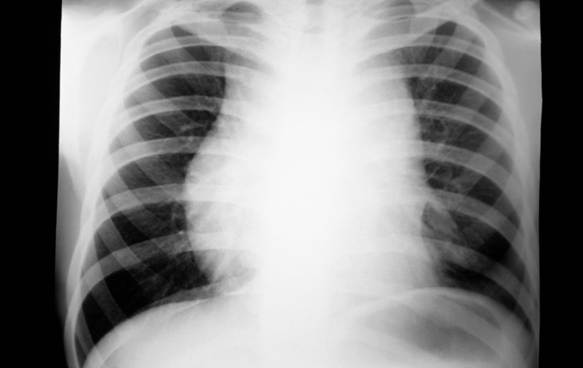

La mayoría de los pacientes con LHC presentan adenopatías no dolorosas o una masa mediastinal que puede presentar o no compresión torácica. La figura 1 es una radiografía de tórax anteroposterior donde se observa un aumento del volumen y la radioopcidad del mediastino, que impide observar la silueta cardíaca. El sitio más frecuentemente afectado es un ganglio linfático (GL) cervical en más del 70 % de los casos, seguido de las regiones mediastínica, axilar y paraaórtica. La afectación extraganglionar primaria se puede encontrar en huéspedes inmunocomprometidos y la afectación de la médula ósea, aunque no es común, se encuentra más frecuentemente en el LHC Depleción Linfocítica que en los otros subtipos.(6)

Fig. 1. Crecimiento mediastinal en Linfoma de Hodgkin.

Fuente: Manual Merck de Diagnóstico